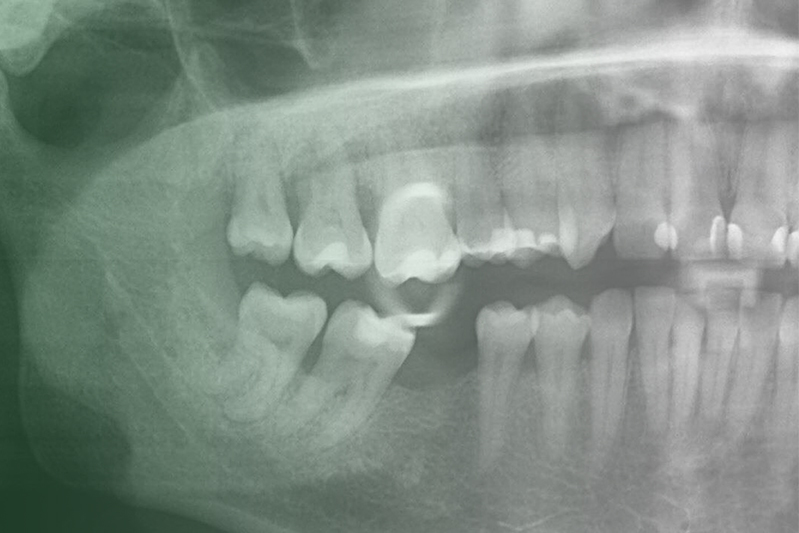

Клинический случай. Эндодонтия

03 марта 2020